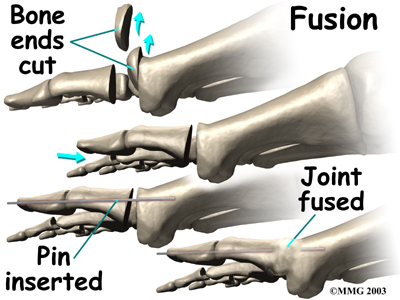

Many surgeons prefer arthrodesis, or fusion, of the MTP joint to relieve the pain. To fuse a joint means to encourage the two bones that form a joint to grow together and become one bone. To perform a fusion, an incision is made into the MTP joint. The joint surfaces are removed. The two surfaces are then fixed with either a metal pin or screw, with the toe turned slightly upward to allow for walking. The bones are then allowed to fuse. The fusion usually takes about three months to become solid.This results in a joint that no longer moves. Wearing a rocker-soled shoe is usually necessary following a fusion to improve your gait.